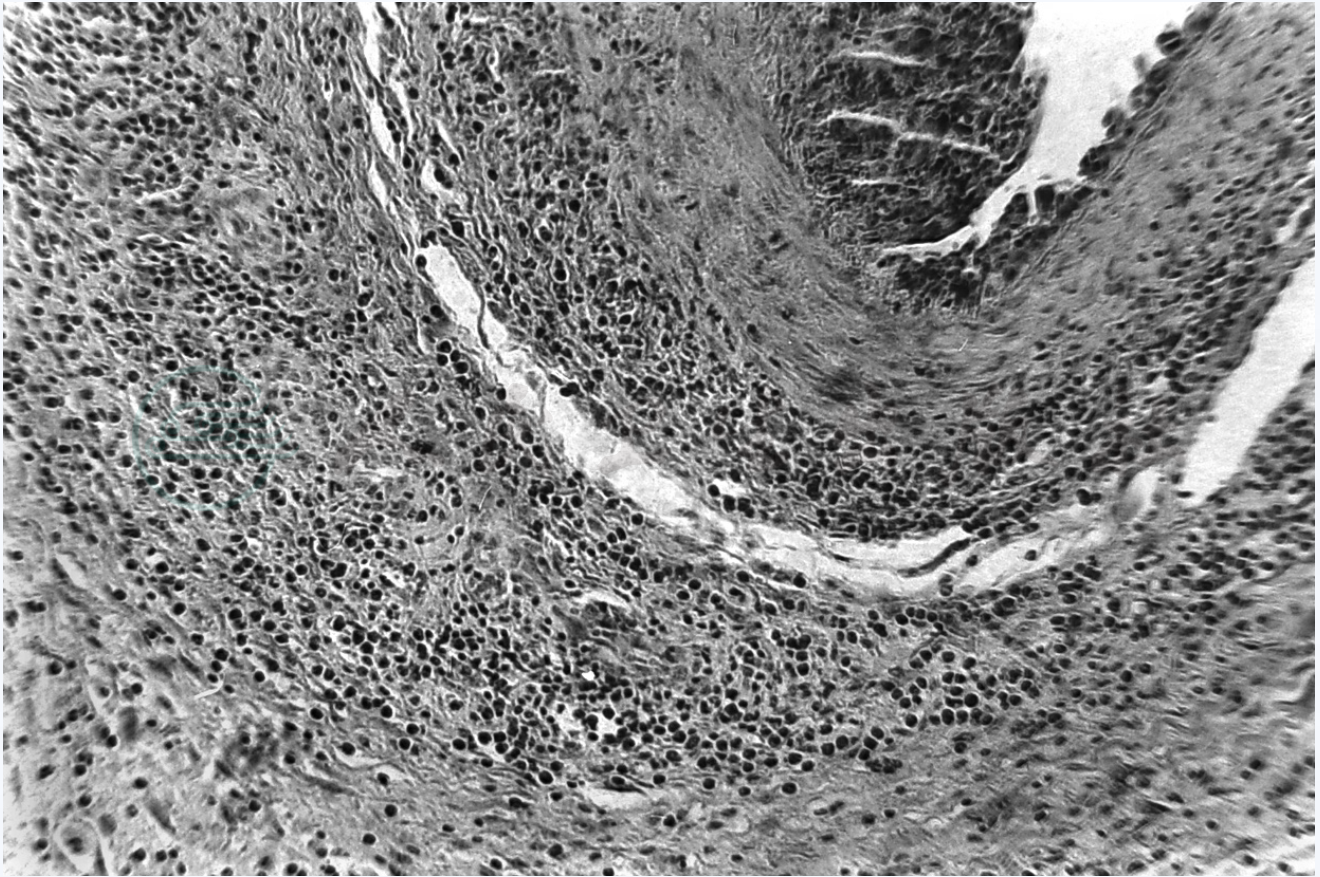

本病的典型病变为,颞动脉及其他颅动脉发生闭塞性巨细胞肉芽肿性全动脉炎。原发病变为内弹性膜变性,导致巨噬细胞吞噬其变性部分,并演变成多核异物巨细胞。异物巨细胞性肉芽肿主要见于中膜,中、外膜和中、内膜之间尚见组织细胞和浆细胞浸润,内膜因有明显纤维蛋白样物质沉积或纤维化而增厚。管腔部分或完全闭塞(图1)。

图1 颞巨细胞动脉炎

注:右上方示颞动脉横切面的一部分,内膜部分纤维化,外膜及其周围可见组织细胞和浆细胞浸润。